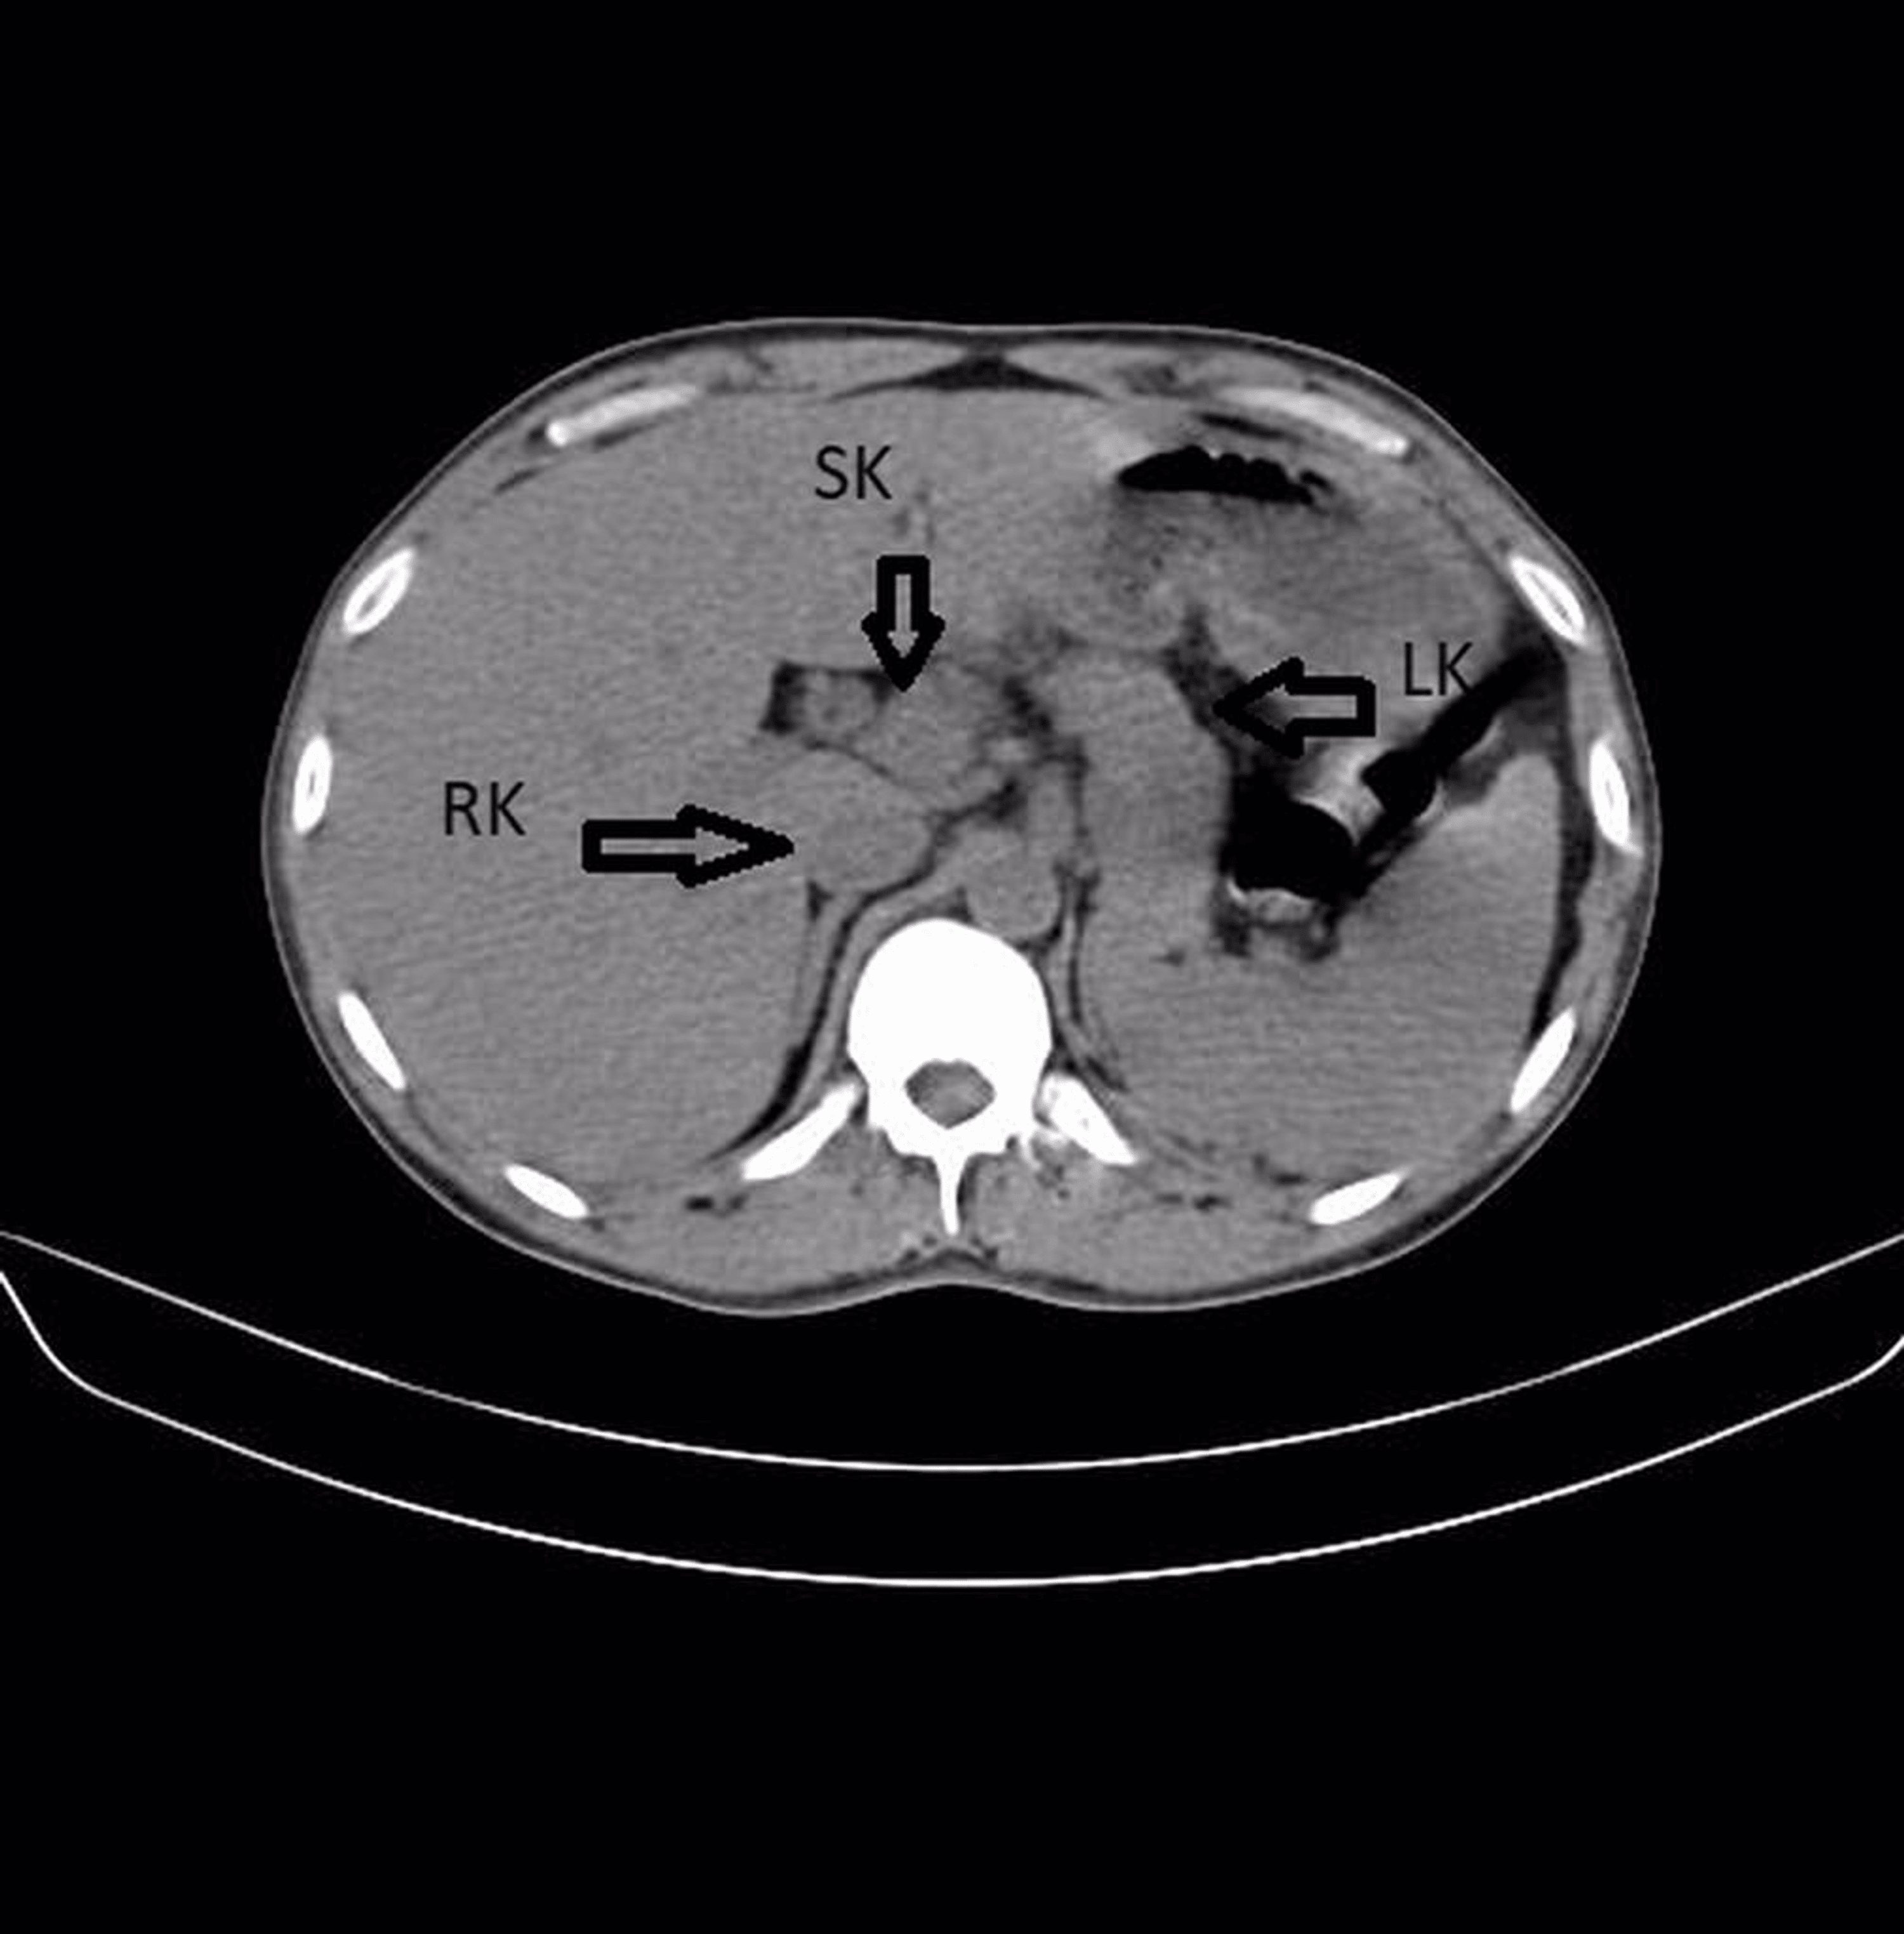

Figure 1 from Laparoscopic heminephrectomy of a horseshoe kidney with giant renal cell carcinoma Horseshoe Kidney Or Renal Fusion horseshoe kidney, or renal fusion, occurs when two individual kidneys fuse together as they rise from the lower belly. horseshoe kidney is when the 2 kidneys join (fuse) together at the bottom. if your child has horseshoe kidney, also called renal fusion, you’ve probably got a lot of questions. They form a u shape like a horseshoe.. Horseshoe Kidney Or Renal Fusion.